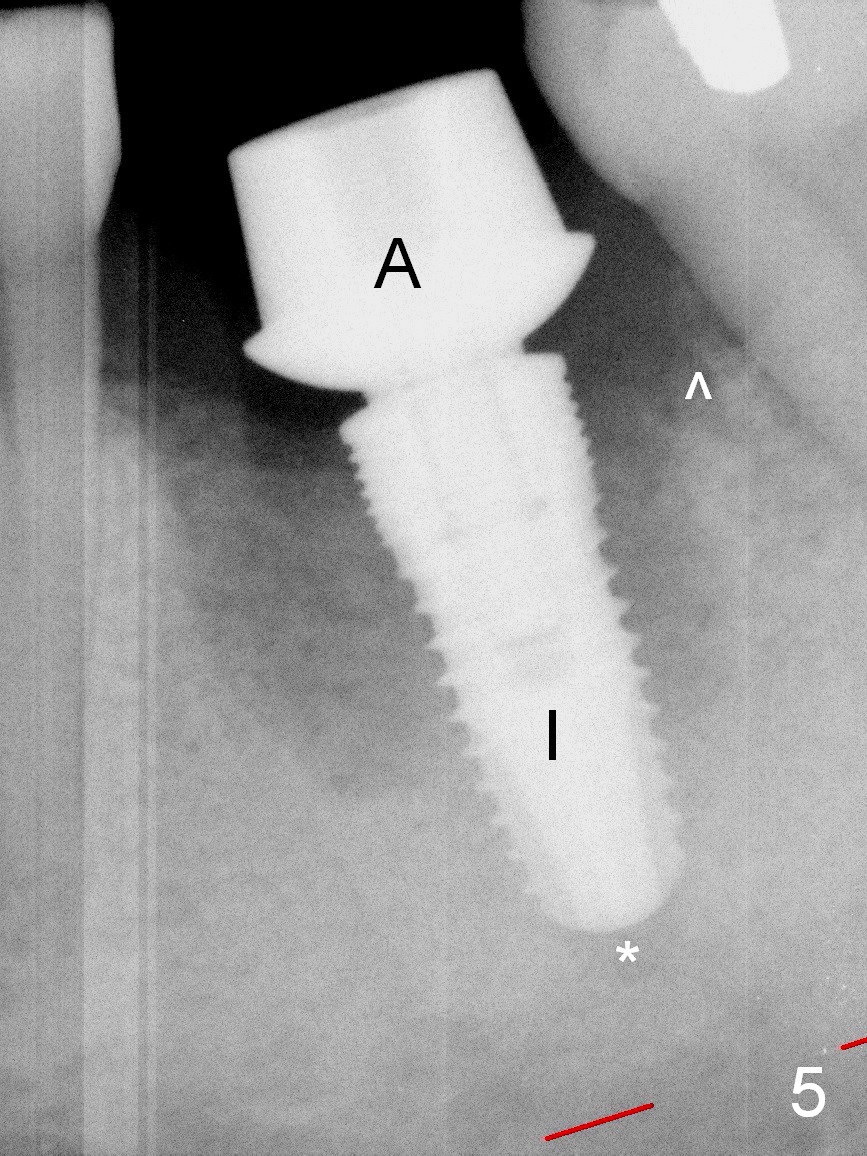

A 37-year-old lady (MP) presents to clinic with chief complaint of bad smell from lower right crown (Fig.1: #19; red dashed line: superior border of the Inferior Alveolar Canal). One of the most prominent pathologies is fracture of the distal root (<). After extraction, the socket is treated with 2% Xylocaine/1:50,000 Epinephrine. The coronal distobuccal plate is defective. Osteotomy is initiated as lingual as possible. The 1st intraop PA shows that the osteotomy is shallow and distal to the almost non-existent septum (Fig.2 S). The osteotomy is intended to move more mesially, but the result is not obvious when 4.5x14 mm drill is in place (Fig.3 D). The depth of the osteotomy is increased by 3 mm; a 5x17 mm tap is stable (Fig.4 T). A 5x12 mm implant (Fig.5 I) is placed until it cannot be turned. The implant is higher than the distal crest (^). In addition there is space apical to the implant (Fig.5*). After 5 mm drill is used, the implant is seated deeper with insertion torque < 35 Ncm (Fig.6). It suggests overprep. Anyway, an immediate provisional is fabricated after placement of an abutment (A). After reline, the provisional fits well. It has to be removed with forceps for occlusal adjustment. Finally the abutment/implant complex turns in the socket with fingers. The rotation/position of the complex is randomly adjusted. When the provisional is cemented, it does not seat completely, but is stable. If the implant osteointegrates, the provisional must play a role in stabilizing the implant. Bone graft is placed in the gap prior to cementation (Fig.6 *).

When the patient returns 1.5 months postop, the provisional has been fractured (Fig.8 lingual view). The abutment is loose. Intraop analysis of a PA shows existence of the peri-implant defect (Fig.7). When the abutment is removed, the implant is found to be stable. As a new smaller abutment (Fig.9: 6.8x4(3) mm) is being torqued at 35 Ncm, the abutment/implant does not turn. Impression for final restoration is taken. Postop analysis of PAs in Fig.6,7 shows that the peri-implant defect has been reduced in 1.5 months. Immediately postop, the fourth coronal large thread is buried in the solid bone, whereas 1.5 months postop the third thread appears inside the base bone.